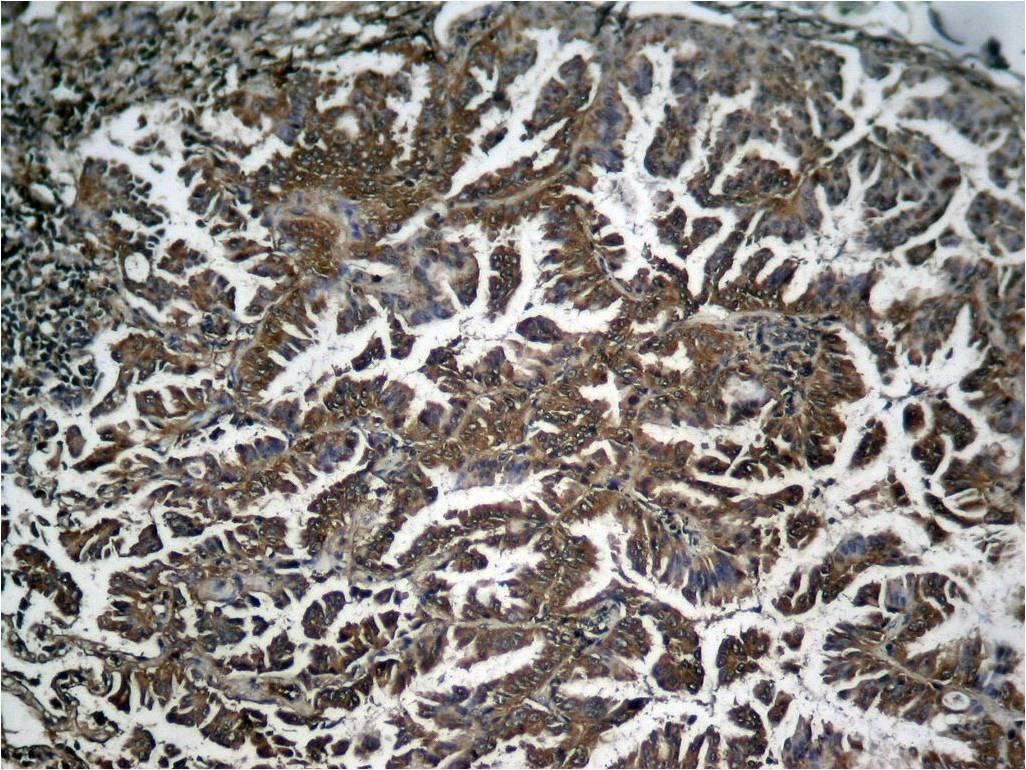

| Verified Activity | 1. Western blot analysis of extracts from HepG2 and HL60 cells untreated or treated with TNF using NFkB-p65 (Phospho-Ser536) Antibody TMAC-02814. 2. Immunohistochemical analysis of paraffin-embedded human breast carcinoma tissue using NFκB-p65 (Phospho-Ser536) Antibody TMAC-02814 (left) or the same antibody preincubated with blocking peptide (right). 3. Immunofluorescence staining of methanol-fixed Hela cells using NFkB-p65 (Phospho-Ser536) Antibody TMAC-02814. 4. Immunohistochemical analysis of paraffin-embedded human breast carcinoma tissue using NFκB-p65 (Phospho-Ser536) Antibody TMAC-02814. 5. Immunohistochemical analysis of paraffin-embedded human Lung carcinoma tissue using NFκB-p65 (Phospho-Ser536) Antibody TMAC-02814. 6. Immunofluorescence staining of methanol-fixed MEF cells using NFκB-p65 (Phospho-Ser536) Antibody TMAC-02814. ![]() ![]() ![]() ![]() ![]() ![]() |